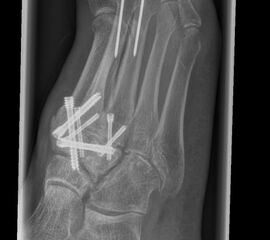

• Temporäre Fixierung mit 1,6 K-Drähten, BV- Kontrolle. Bei korrekter Stellung definitive Osteosynthese entweder mit je 2 Kompressionsschrauben, Platten oder Klammern.

• Die mechanisch stabilste Situation ist mit dorsalen winkelstabilen Platten, optional mit Kompressionsschraube zu erreichen 3.

• BV-Kontrolle von Stellung der Knochen und der Lage des Osteosynthesematerials.

• Röntgenkontrolle nach 8-10 Wochen, dann - je nach knöchernem Durchbau - Übergang zur Vollbelastung im Konfektionsschuh (Abb. 24 und 25).